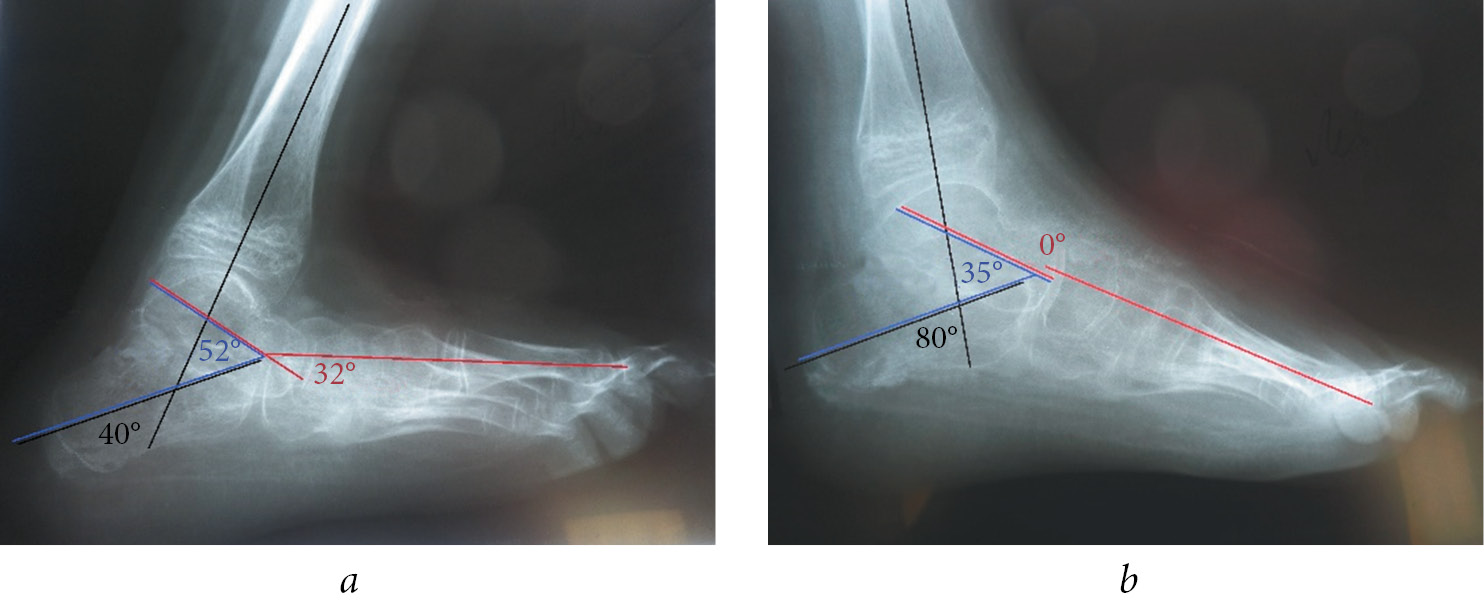

Clinical example (Fig. 2). Patient L., 11 years old. The patient was diagnosed with myelocele and neurogenic calcaneal deformity of the left foot. He complained of difficulty in walking, with support on his left heel bone. Clinically, the left foot was extended at 30°. Active foot movements are possible only with foot extension. The strength of the left tibial muscles was 5, 0, 0, 2, and 2 points in the anterior tibial muscle, peroneal (short and long) muscles, flexors and extensors of the toes, posterior tibial muscle, and a posterior group of tibial muscles, respectively. The foot was passively brought to the middle position “springy”, but not maintained. Ankle flexion was impossible. Radiograph of the left foot showed calcaneal deformity, the vertical position of the calcaneus, 40° for the calcaneotibial angle, 32° for Meary’s angle, and 52° for the sagittal astragalocalcanean angle. One-stage correction of the deformity was performed after considering the possible passive correction of the foot to the middle position and the child’s age. The release of the foot joints (subtalar, astragaloscaphoid, calcaneocuboid, and cuneonavicular) was performed with grafting of the tendon of the anterior tibial muscle to the calcaneal tubercle; fixation of the foot with wires with slight hypercorrection (20° bending of the foot for 2 months) was performed. The foot is fixed in the splint after surgical hardware removal. Clinically, the foot is in the middle position, with support on the entire plantar surface of the foot. The X-ray image shows improvement in the osteo-articular relations in the foot, calcaneotibial angle of 80°, Meary’s angle of 0°, and sagittal astragalocalcanean angle of 35°.

Fig. 2. Patient L., 11 years old, with a diagnosis is neurogenic calcaneal deformity of the left foot: a — radiograph of the left foot in lateral projection upon admission: calcaneotibial angle is 40°, Meary’s angle is 32°, sagittal astragalocalcanean angle is 52°; b — radiograph of the left foot in lateral projection after the surgical treatment: calcaneotibial angle is 80°, Meary’s angle is 0°, sagittal astragalocalcanean angle is 35°